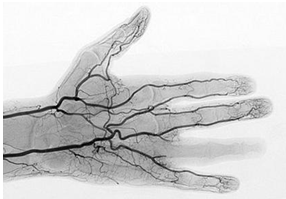

人体脉络

“诸脉之浮而常见者,皆络脉也。”“当数者为经,其不当数者为络也。”显然,经络是皮肉之间肉眼可见的管道,大而数目少的叫经脉(即现代医学的大动脉和静脉),小而数目多得无法数的叫络脉(小的浅表静脉网和毛细血管)。

从功能看,经络里运输的是血和气。古人言之凿凿,“脉者,血之府也”,“血之随气,循环经络”、“血循经脉”等等。中医有“血病身有痛者治其经络”(《黄帝内经》三部九侯论篇),“心者血,肺者气。血为荣,气为卫,相随上下,谓之荣卫。通行经络,营周于外”(《难经?论脏腑》),实际上就是在说经络中走的是血,有气为护。可见,经络就是血管。